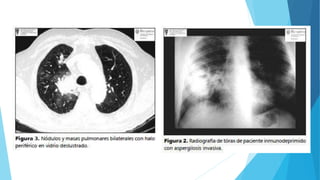

Imagenología

 Infiltrado pulmonar unilateral

basal derecho